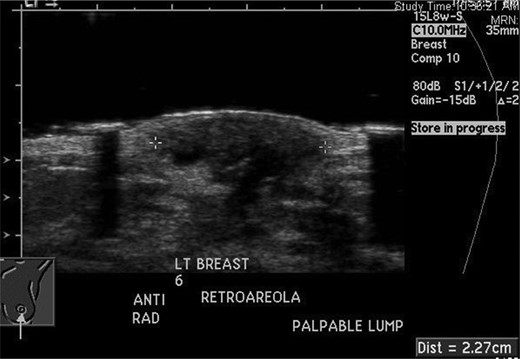

She returned to clinic later in January after the ultrasound, which revealed a 1.4 × 0.9 × 1.8 cm fluid collection at the 6 O'clock position most likely representing a hematoma; BIRADS #3 likely benign recommend short-term follow-up. She was scheduled for a repeat ultrasound in April 2012 with follow-up in breast clinic following the ultrasound. Repeat ultrasound (seen in Fig. 2) revealed a stable fluid collection measuring 1.5 × 1.2 × 2.2 cm, once again BIRADS #3 likely benign recommend short-term follow-up with the breast surgeon. She was seen in clinic following the ultrasound in April and reported decreasing pain and no nipple discharge, she was given a 1-month follow-up appointment.